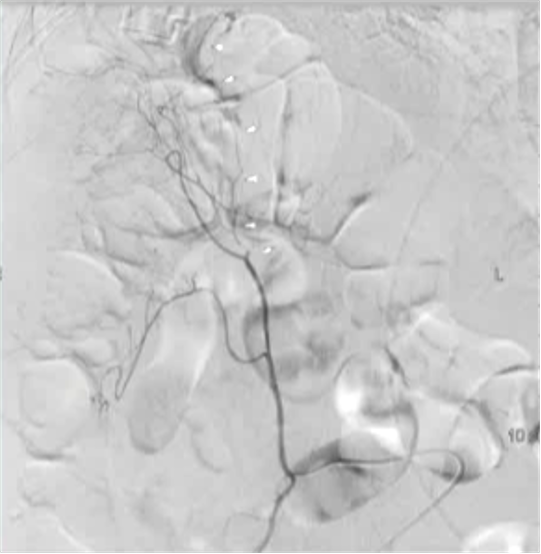

病例二

100/50 mmHg

20 μց Arterenol 170/80 mmHg

病例3 80/50 mmHg

40 μg Arterenol 170/90mmHg

|

出血点, |

PVA栓塞 |